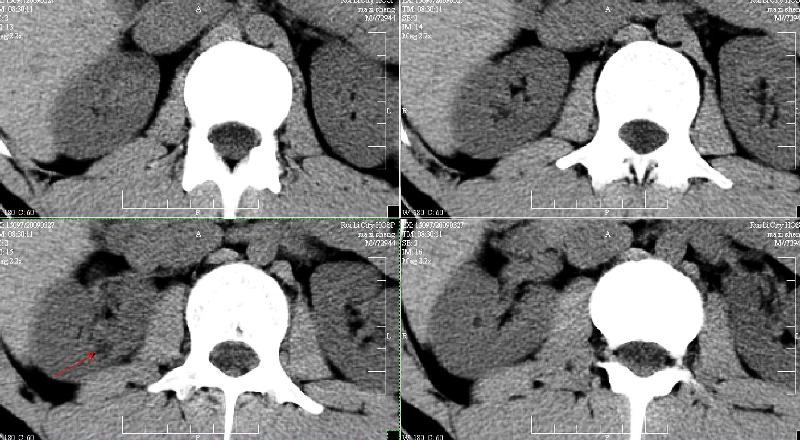

标题: CT19133:M,28岁。 [打印本页]

标题: CT19133:M,28岁。

ct发现左肾小结石而右侧腰部疼痛?右肾是伸入实质的肾盏吗?

增强再看,囊肿可能

建议增强,囊肿可能